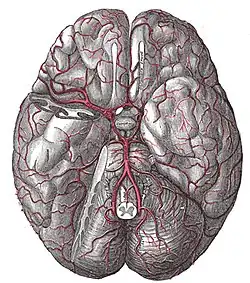

Blutversorgung des Gehirns

(Ansicht von unten, der rechte Schläfenlappen wurde teilweise entfernt)

Vier große Schlagadern versorgen das Gehirn des Menschen und der meisten Säugetiere mit sauerstoffreichem Blut (alte Bezeichnung: „arterielles Blut“). Je zwei liegen auf jeder Seite des Halses, vorn die inneren Halsschlagadern (Arteriae carotides internae) und hinten die Wirbelarterien (Arteriae vertebrales). Das Blut fließt nach der Passage des Gehirns über besondere venöse Hirnblutleiter (Sinus durae matris) ab, die gegenüber den Venen einige Besonderheiten aufweisen.